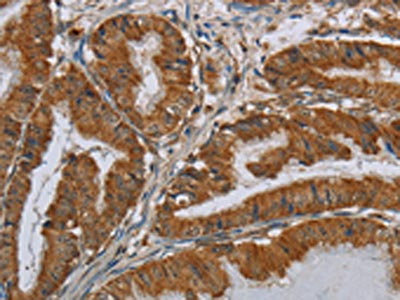

The image on the left is immunohistochemistry of paraffin-embedded Human esophagus cancer tissue using CSB-PA077659(CSH1 Antibody) at dilution 1/40, on the right is treated with fusion protein. (Original magnification: ×200)